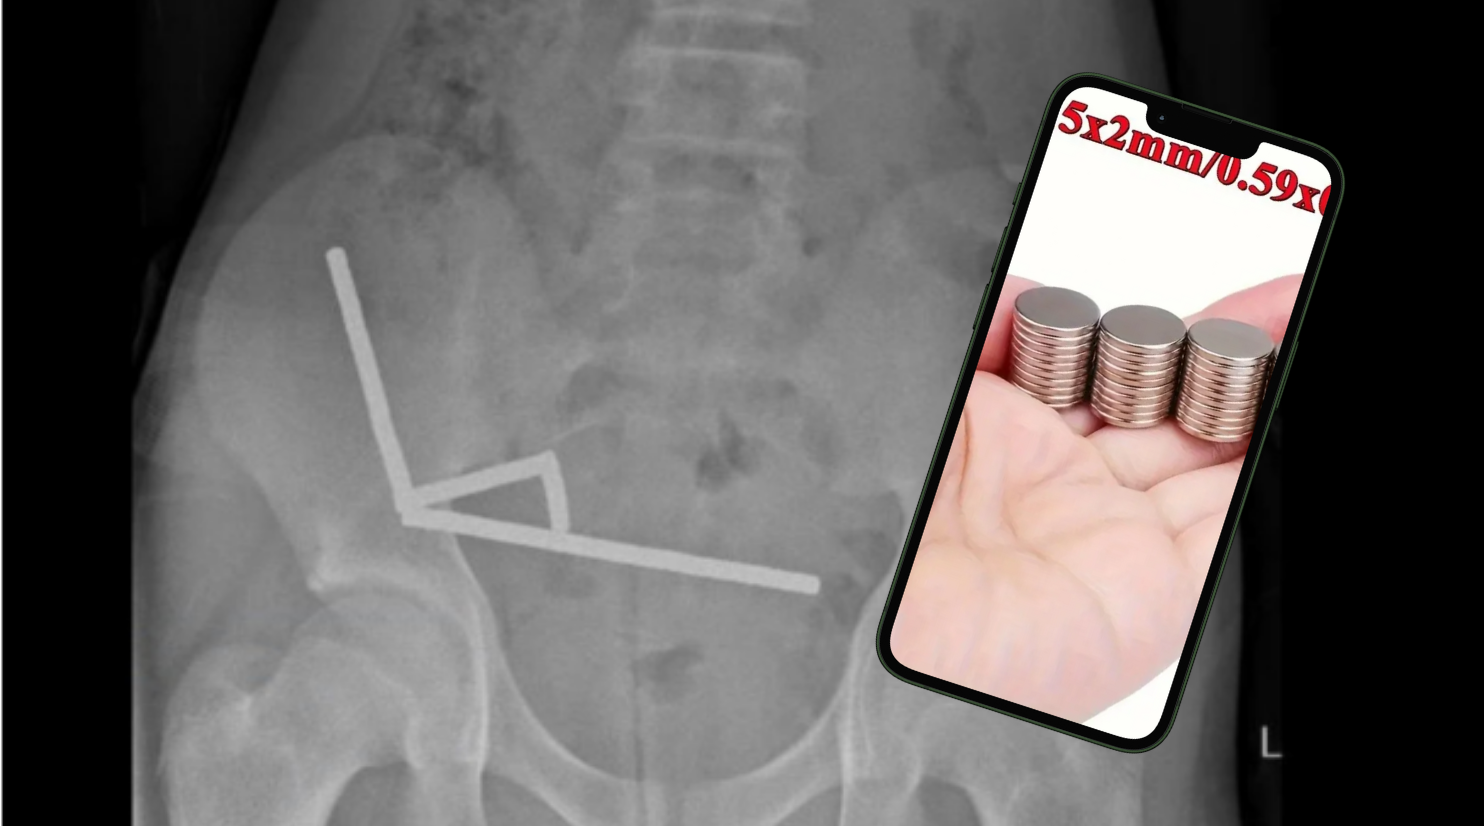

Tras asistir a un centro médico producto de malestares que presentó el menor en la zona del estómago, se percataron que en la radiografía aparecían “cuatro cadenas lineales de imanes” unidas, consigna la revista People.

Eran entre 80 y 100 imanes de alta potencia (neodimio), de 5 x 2 milímetros.

Y es que los riesgos pueden ser graves, como por ejemplo el de este caso, ya que las imágenes mostraron que los imanes “parecían estar en partes separadas del intestino (…) adheridos debido a las fuerzas magnéticas”.

Imagen de referencia | Imanes de neodimio | Temu